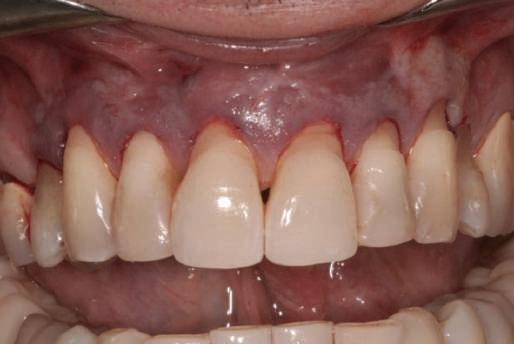

Cazul (3): Refrezarea bonturilor individualizate

Figurile

9. Bonturile de vindecare.

10. Bonturile individualizate în prima etapă.

11. Recesia evidentă în jurul bonturilor din prima etapă, după extracţiile adiacente şi inserarea implanturilor din faza a doua.

12. Bonturile refrezate şi noile bonturi individualizate.

în timp ce toate bonturile individualizate au fost fabricate şi/sau frezate în laborator. Fig. 12 prezintă plasarea bonturilor refrezate (la implanturile din prima etapă) şi bonturile individualizate noi (la cele din a doua etapă).